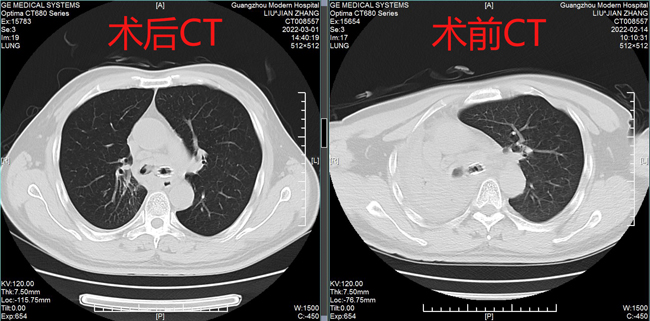

術(shù)前術(shù)后CT表現(xiàn)

據(jù)黃德良主任介紹,劉健患者這次因肺鱗癌引起氣喘問題過來求治的。入院后經(jīng)過完善檢查診斷為右肺鱗癌并胸膜、肺門、縱膈淋巴結(jié)轉(zhuǎn)移,已是T4N2M1屬于肺癌IV期了?!爱?dāng)時情況非常緊迫,患者右主支氣管主干完全堵塞,左主支氣管堵塞,雖然之前在外院做了支架,但支架近端也有腫瘤導(dǎo)致大部分的堵塞。病人呼吸困難,經(jīng)皮血氧低于80%。在麻醉科,氣管鏡室和8樓醫(yī)護共同努力下給病人行右主支氣管腫物微波消融術(shù),術(shù)后氣道恢復(fù)通暢,右肺完全復(fù)張!患者手術(shù)中還出行反復(fù)出血,情況非常不理想,幸得患者家屬無條件的信任,經(jīng)過團隊的共同努力,歷時3個多小時的手術(shù)還是順利完成。目前病人已經(jīng)可以下床走路,經(jīng)皮血氧恢復(fù)至95%。”2月15日,經(jīng)過黃教授團隊的評估后,患者接受了介入化療方案,術(shù)后患者呼吸困難癥狀得到進一步改善,指尖血氧好轉(zhuǎn)。在2月20日再次接受氣管鏡下雙側(cè)主支氣管腫物微波消融術(shù)。3月1日復(fù)查了CT,患者腫塊縮小,右肺復(fù)張。